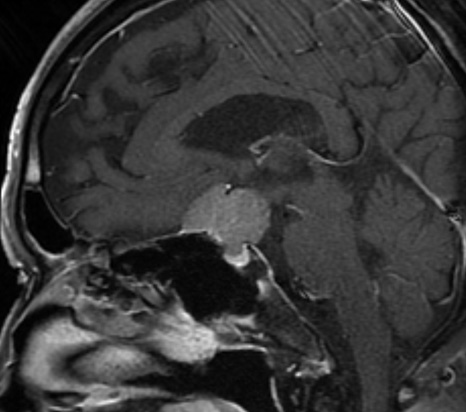

トルコ鞍の中で成長し、大きくなるとトルコ鞍から頭蓋内へ突出し(鞍上部へ突出し)、脳神経を圧迫します。腫瘍が鞍上部へ突出し視神経を強く圧迫すると、視機能の低下(視野欠損、視力低下)を招きます。視野欠損は両耳側半盲といって、両目の外側(左右の目の耳側)の視力が欠けてしまいます。この状態になると、人混みでぶつかり易くなったり、車の運転で衝突事故を起こしやすくなります。

トルコ鞍内から鞍上部にかけて発生しますが、鞍上部に発生することが一般的です。